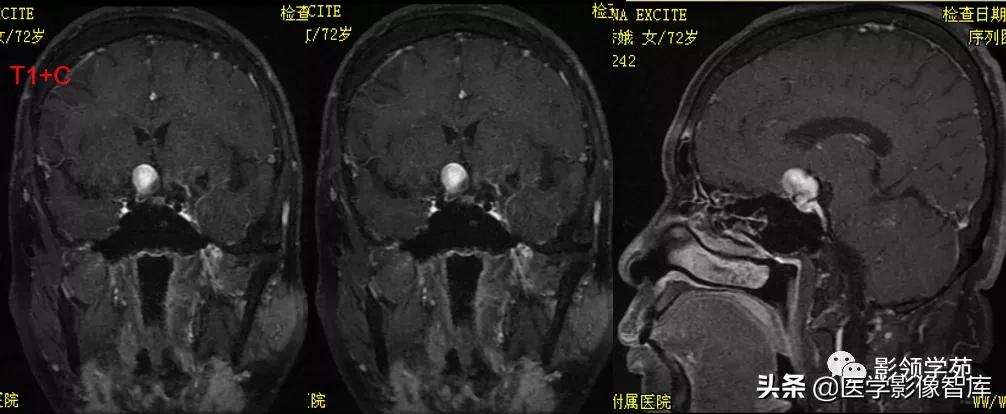

女 72岁,发现糖尿病3年余

鞍上区见一团块状稍高密度影,边界尚清,密度均匀。

鞍上右上方见一类椭圆形流空影。

病灶明显强化(瘤内血栓未强化),边界清楚,与右侧颈内动脉海绵段分界不清。垂体大小、形态未见异常。